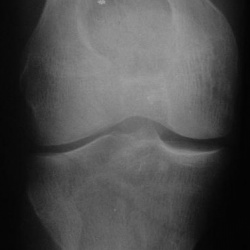

Пациентка жалуется на боль в обл. внутр. мыщелка б.берц кости. Снимки мерзкого качества, но это все, что есть, временной интервал - около года (9 - 10 гг). Прилагаю КТ на пленке. Наша версия -...